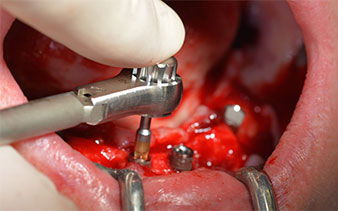

This corresponds to the next preset position in the Implantmed. Here we see the W&H contra-angle handpiece being held at a 45° angle to mesiocaudal in the region of 45 in order to preserve the mental nerve. The mental foramen is used as the anatomic reference for all drilling in this region. The subsequent holes were drilled at a reduced speed of 300 rpm (Fig. 10 and 11).